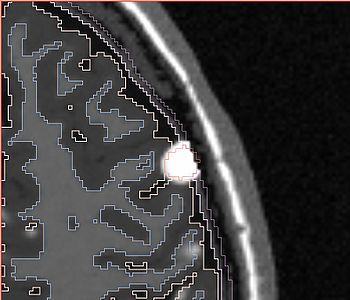

NOTE: red outlines the boundary of the label corresponding to the initial tumor seed!

All the following experiments are based on the "thin dura" input labels, and the tumor seed image shown on the right. The tumor label is shown in green color. Note that the tumor is touching the gray matter label.

The following screenshots capture the same axial slice (#119) of the following images in order: (1) image containing the tumor probabilities, and (2) the simulated Gad enhanced image, both overlayed with the warped tumor/brain tissues labels.

Poisson ratio 0.5

(initial value)

Note very very minimal deformation of the surrounding brain tissue, although the tumor volume increased, for Poisson=0.5.